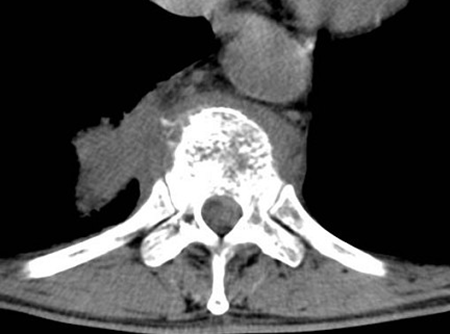

180、单项选择题

女,68岁,头部剧痛伴左上肢无力半月余,近两天发展为双下肢截瘫,请结合影像学检查,选出最可能的诊断()

A.脊髓空洞症

B.椎管内血肿

C.硬膜外脓肿

D.脊膜膨出

E.脊膜瘤

181、问答题 髓外硬脊膜内肿瘤的临床特点是什么?